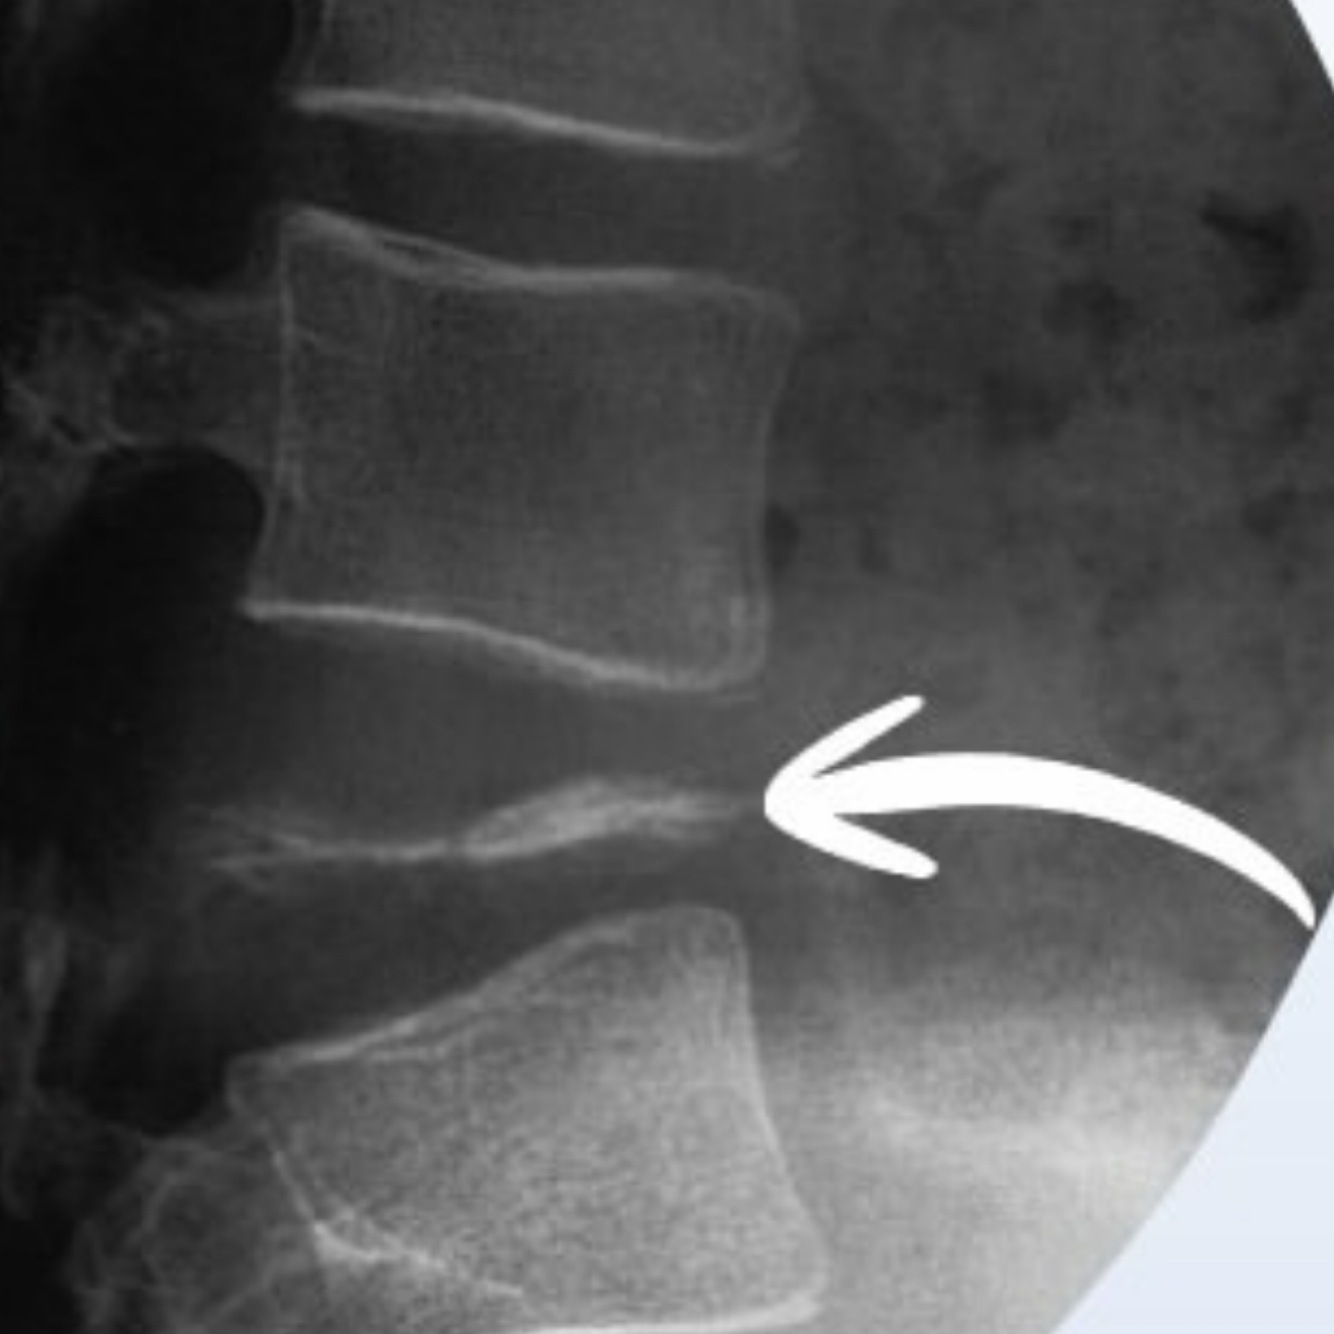

Qual alteração apresentada?

(Entesófito ou osteófito)

A

Entesófito

• O Entesófito tende a ser vertical, no eixo do ligamento

• os discos estão normais

Quais características sugerem entesófito ?

Atentar para espondilite anquilosaste